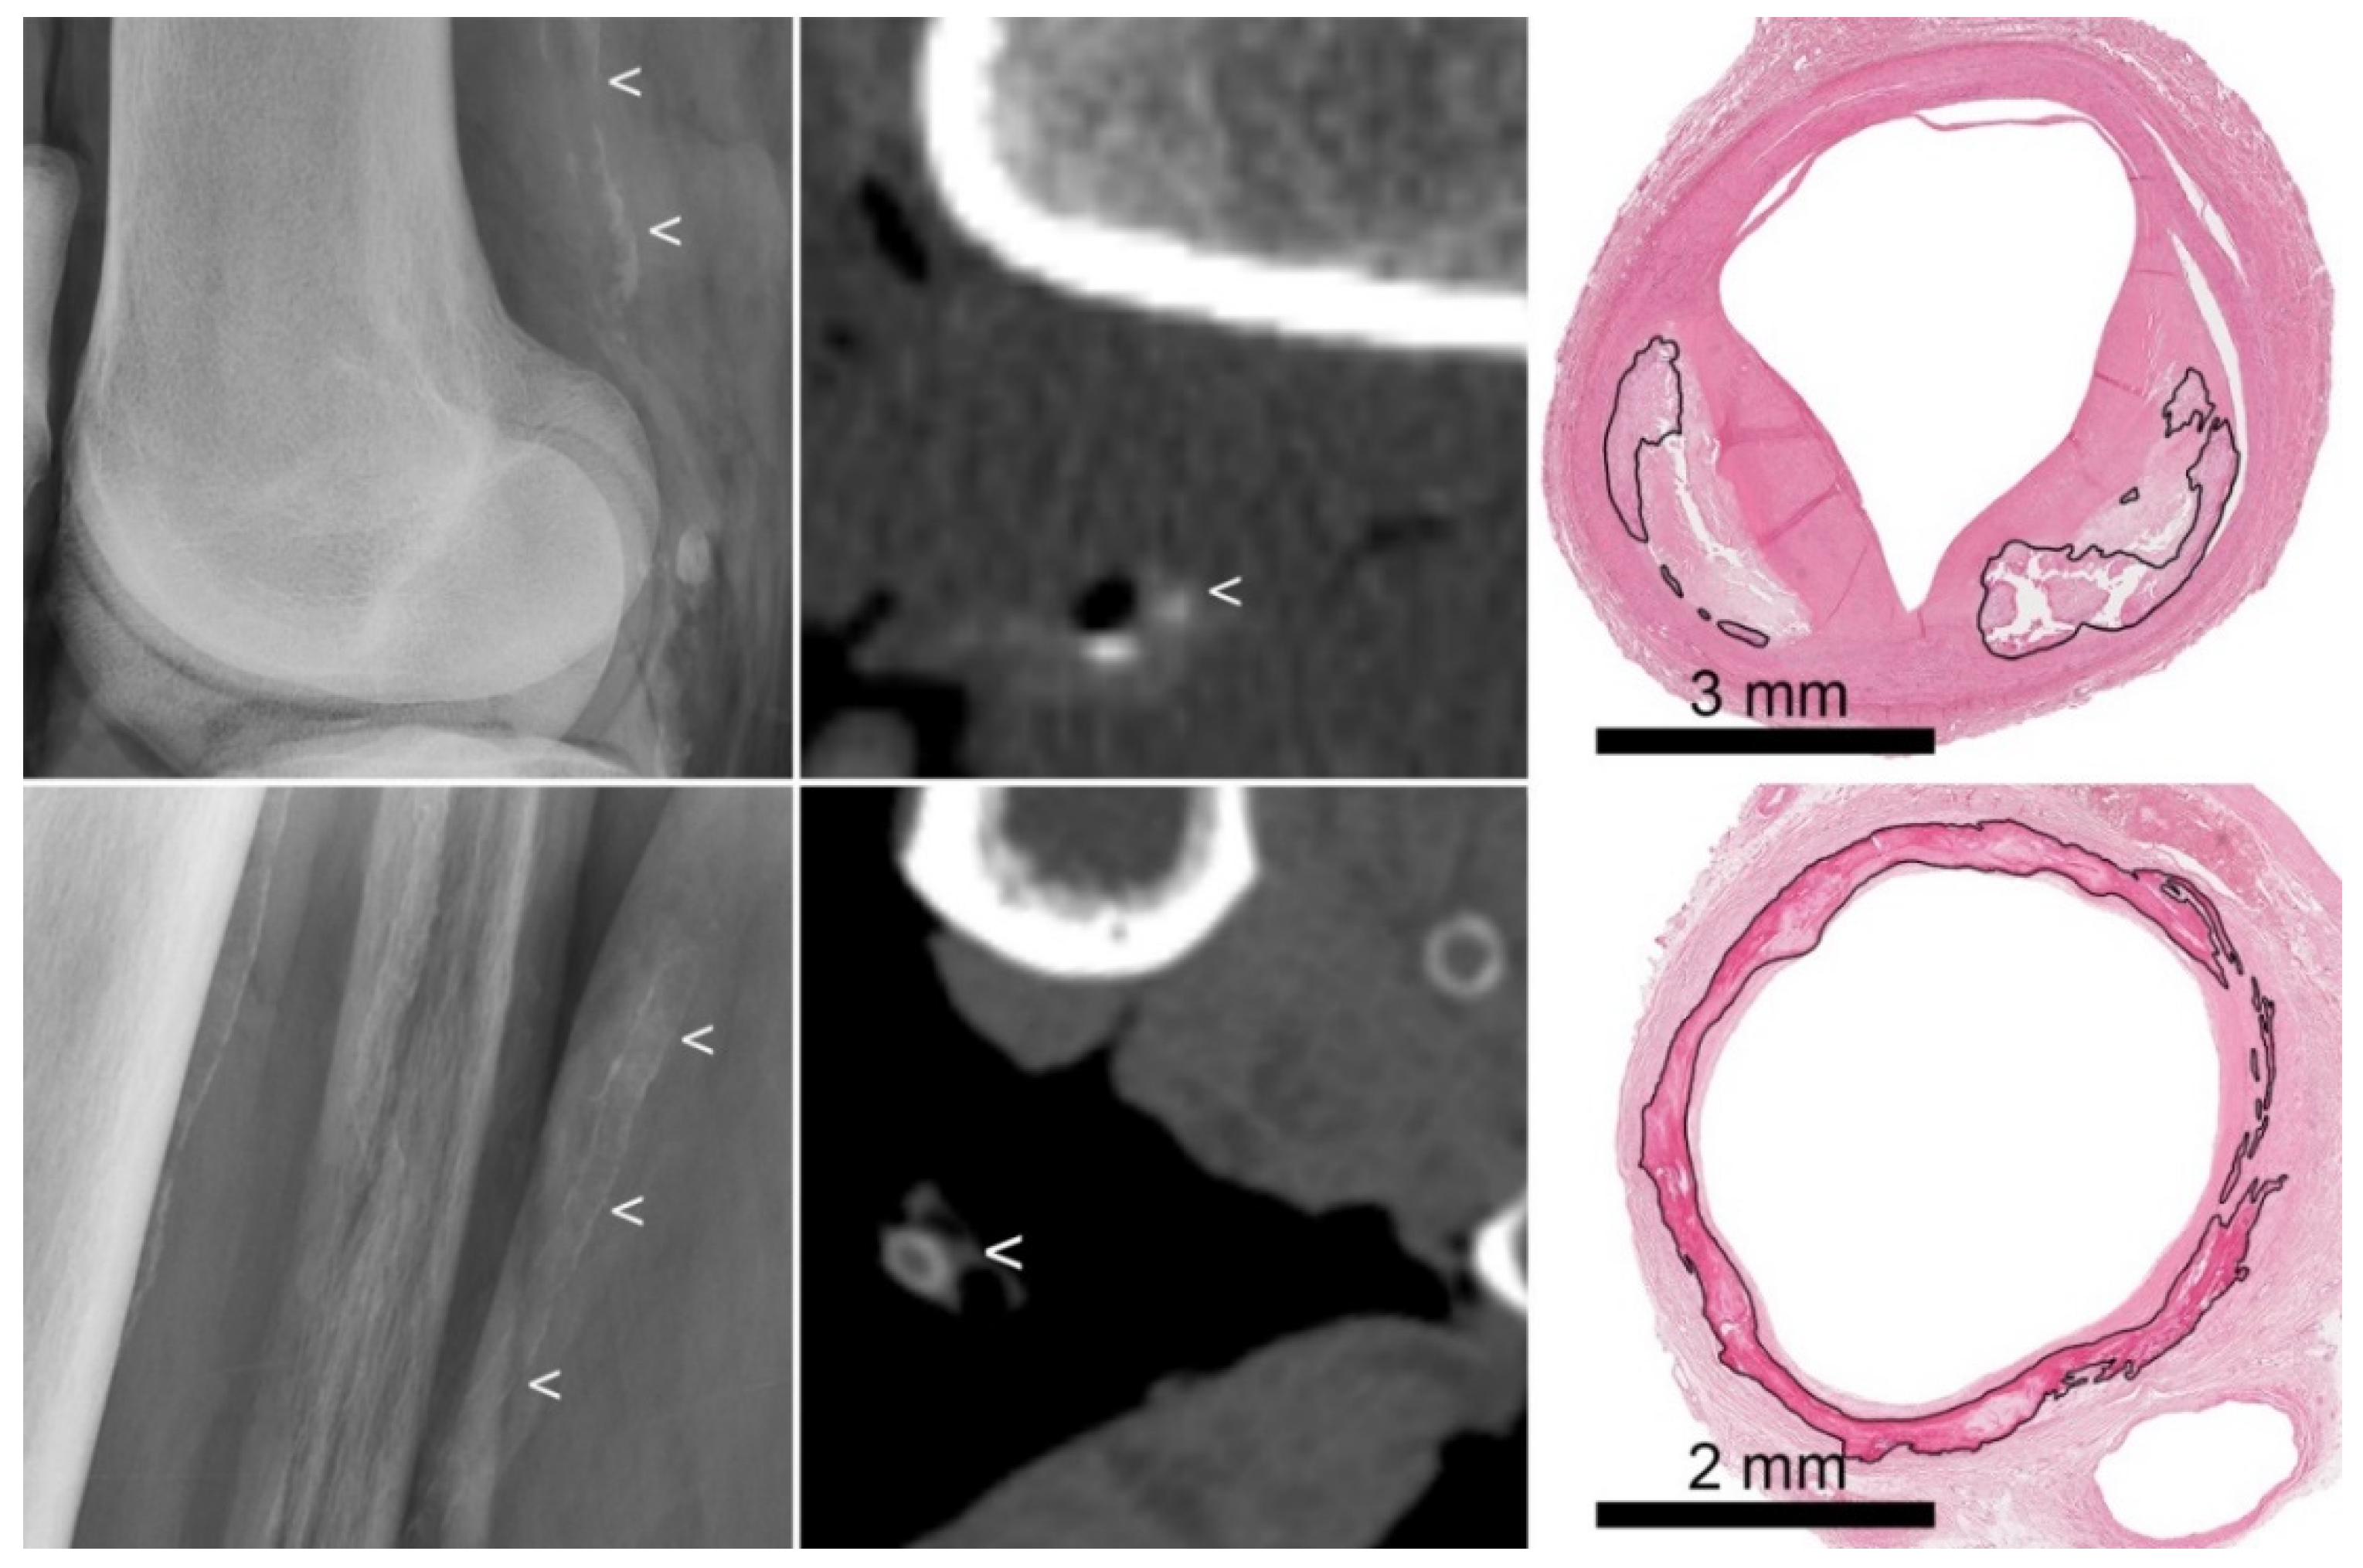

Figure 1.

Examples of intimal and medial calcification on radiograph and CT. (Top row): atherosclerotic intimal calcifications. From left to right: radiograph (showing irregularly distributed thick calcifications (<)), CT (showing thick dots of calcification (<)), and histology (showing calcifications (marked) located in an atherosclerotic plaque). (Bottom row): medial calcifications. From left to right: radiograph (showing regularly distributed thin calcifications along the vascular wall (<)), CT (showing circular thin calcifications (<)), and histology (showing circular calcifications (marked) involving the internal elastic lamina, in the absence of atherosclerosis).